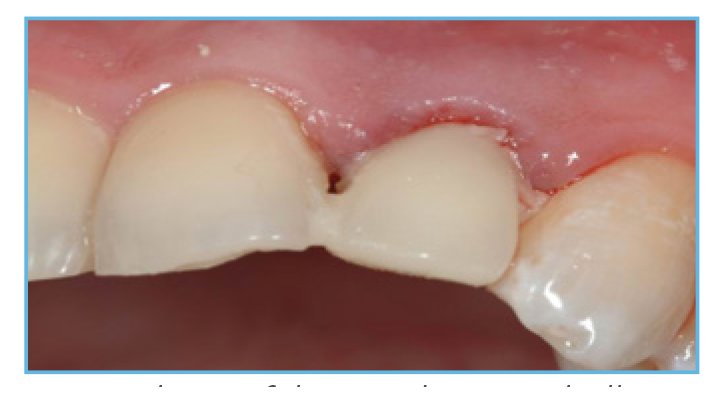

Fig. 4. The prefabricated crown shell was luted to the PreFormance Post.